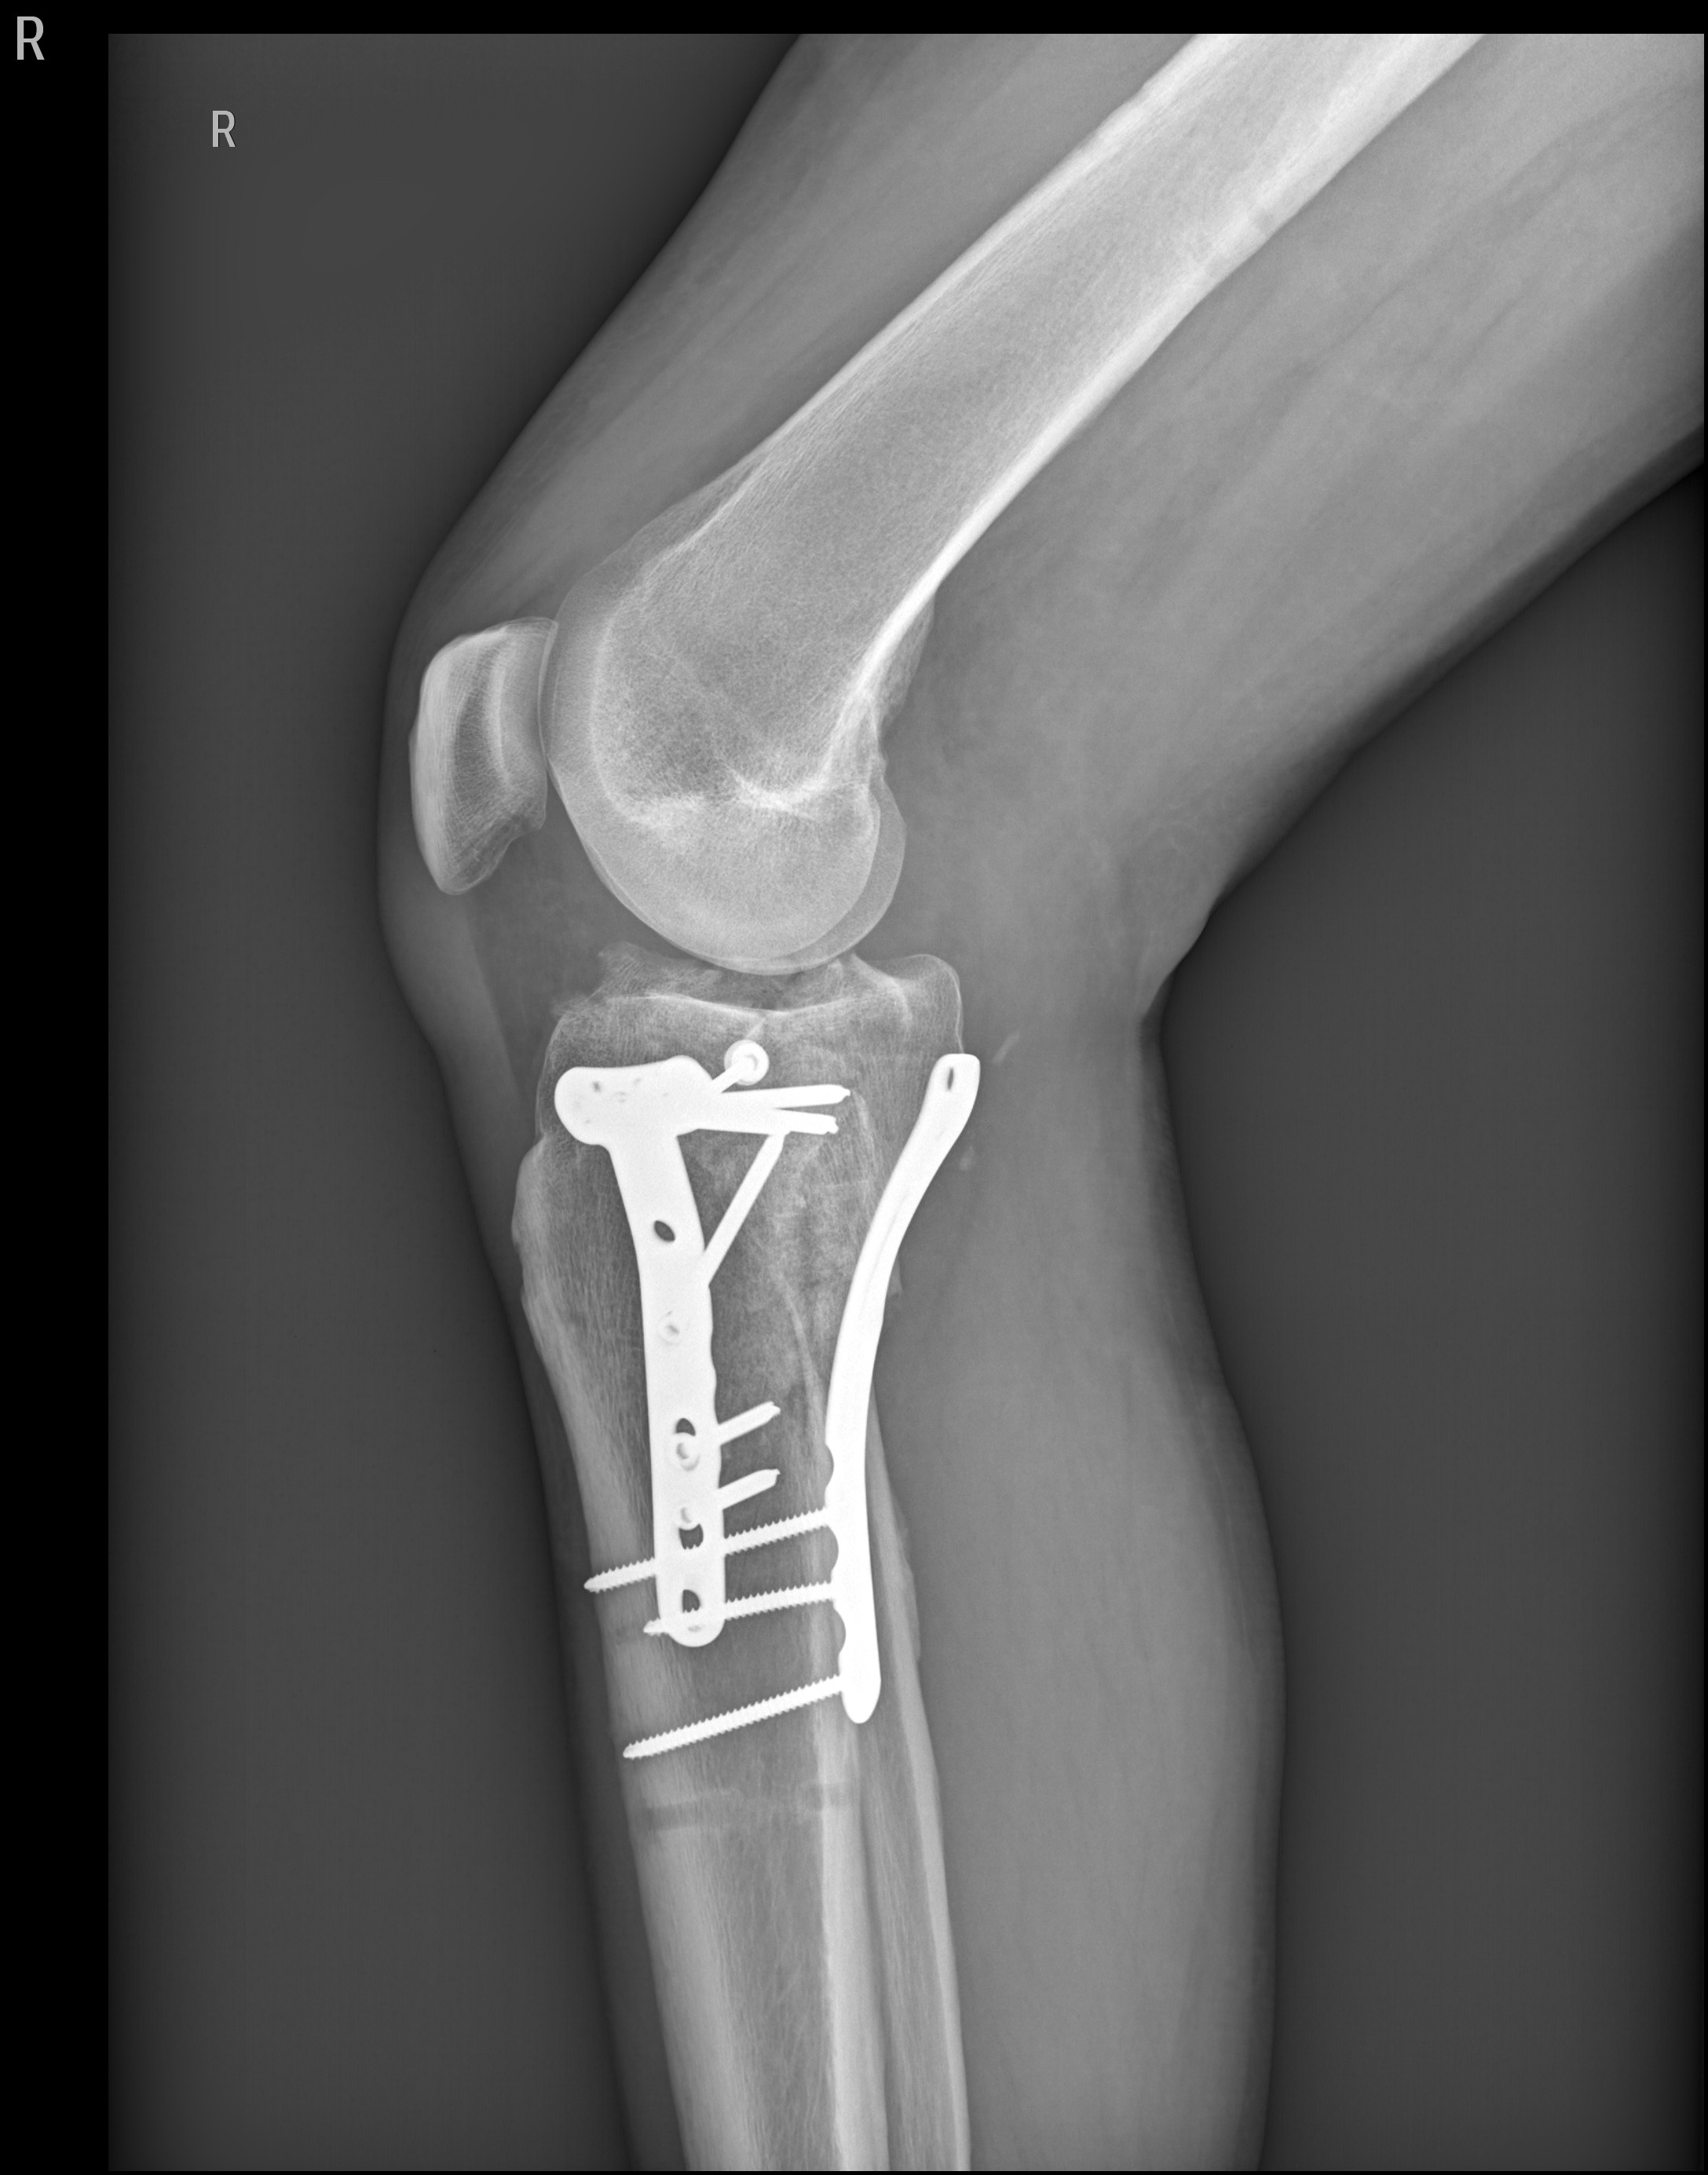

Lange Rede, kurzer Sinn, Schienbein rechts innen durch den Zylinder zerschmettert!

Erstes O.P. Externer Fixateur,

Zweiter O.P.-Bissjen titanium.